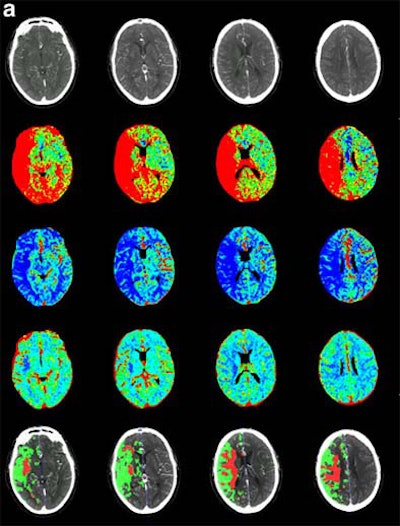

| Recent CT survey of a 62-year-old male patient admitted to our emergency room with a) left hemisyndrome, including a) perfusion CT and b-e) CT angiography (CTA). Above: From the perfusion CT raw data (first line), three parametric maps can be extracted relating to mean transit time (MTT, second line), regional cerebral blood flow (rCBF, third line) and regional cerebral blood volume (rCBV, fourth line), respectively. Applying the concept of cerebral vascular autoregulation leads to a prognostic map (fifth line), describing the infarct in red and the penumbra in green, the latter being the target of thrombolytic drugs. Below: b, c) CTA enables identification of the origin of the hemodynamic disturbance demonstrated by perfusion CT. In this patient, it relates to an occlusion at the right M1-M2 junction (arrows). d, e) Finally, CTA features bilateral calcified atheromatous plaques at both carotid bifurcations (arrowheads). Images courtesy of Dr. Max Wintermark. |